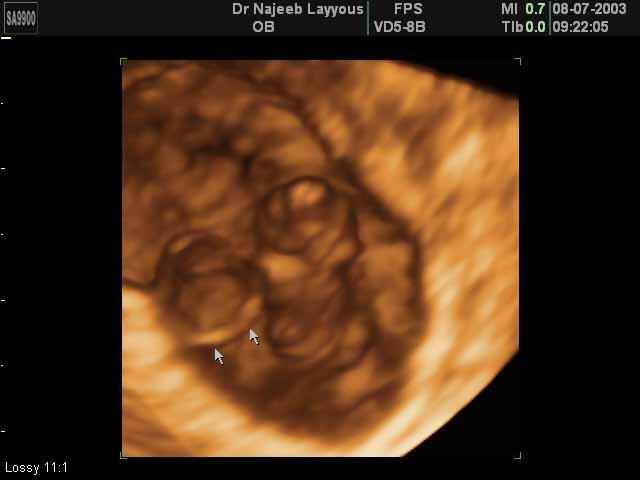

- لقطات فيديو للجنين بجهاز الموجات فوق صوتية رباعي الأبعاد

- صور لوجه الجنين في داخل الرحم

- صور لأعضاء الجنين